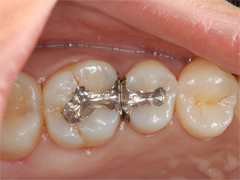

保険診療によるインレー治療がされていましたが、フロスがひっかかることと銀歯を取り替えたいとのことでセラミックスインレーでの治療を希望(当院長治療症例)

不適合な金属に汚れが溜まり、金属と歯とのすき間にむし歯の再発が起きています。